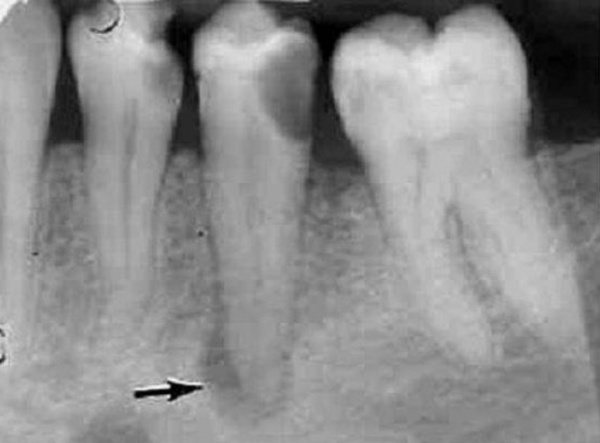

Если периапикальный абсцесс сформировался при обострении хронического фиброзного периодонтита, рентгенографически определяют расширение периодонтальной щели в участке верхушечной трети корня. Характерным рентгенологическим признаком хронического гранулематозного периодонтита является участок деструкции костной ткани округлой формы диаметром до 5 мм вокруг верхушки причинного зуба. При образовании периапикального абсцесса на фоне хронического гранулирующего периодонтита на прицельной рентгенограмме выявляют деструктивные изменения в периапикальной зоне с неровными контурами, напоминающими «языки пламени». Может наблюдаться резорбция корней. Периапикальный абсцесс дифференцируют с острым периодонтитом, обострением хронического периодонтита, пародонтальным абсцессом, периоститом, остеомиелитом, нагноением радикулярной кисты. Клинический осмотр проводят стоматолог-терапевт, стоматолог-хирург.